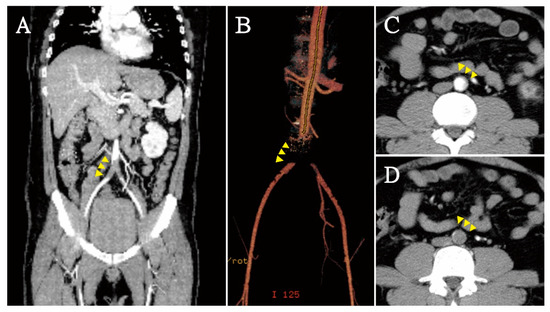

2.4. Imaging Tests